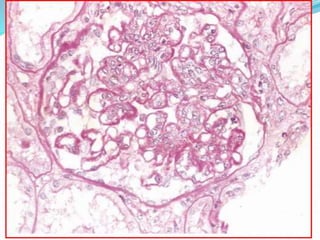

 Kidney-Lupus nephritis affects 50% of SLE patients.

 The principal mechanism of injury is immune

complex deposition in the glomeruli, tubular or

peritubular capillary basement membranes, or larger

blood vessels.

 Five patterns are recognized: minimal mesangial (class

I); mesangial proliferative (class II); focal proliferative

(class III); diffuse proliferative (class IV); and

membranous (class V).

 Kidney-Lupus nephritisaffects 50% of SLE patients.  The principal mechanism of injury is immune complex deposition in the glomeruli, tubular or peritubular capillary basement membranes, or larger blood vessels.  Five patterns are recognized: minimal mesangial (class I); mesangial proliferative (class II); focal proliferative (class III); diffuse proliferative (class IV); and membranous (class V).